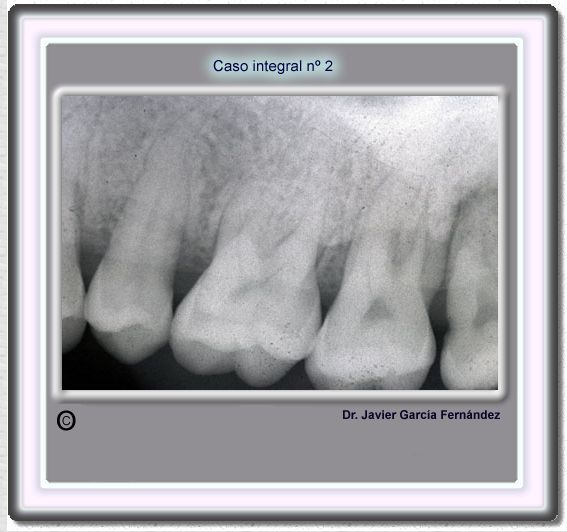

image 16